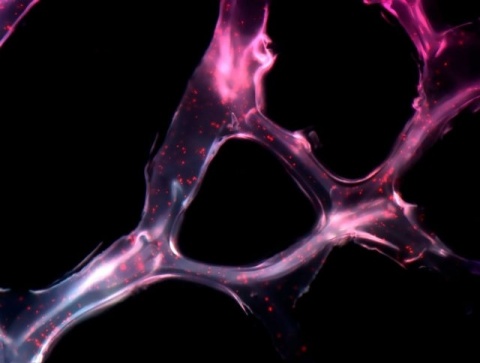

Minibomba osmótica utilizada como dispositivo para la administración del análogo de hormona tiroidea TRIAC directamente al ventrículo cerebral de los ratones mediante cánulas implantadas. (Foto: UAM)